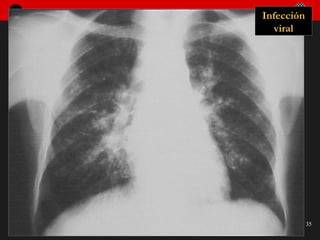

Infección viral

Fibrosis post-infección viral

Infección pulmonar intersticial: Evolución Inflamación de la pared bronquiolo-alveolar Edema y hemorragia, extensión parcheada Generalización de edema intersticio-alveolar a. Resolución b. Fibrosis: patrón reticular 1.  2.  3.

Infección pulmonar intersticial:Evolución Inflamación de la pared bronquiolo-alveolar Edema y hemorragia, extensión parcheada Generalización de edema intersticio-alveolar a. Resolución b. Fibrosis: patrón reticular 1. 2. 3.